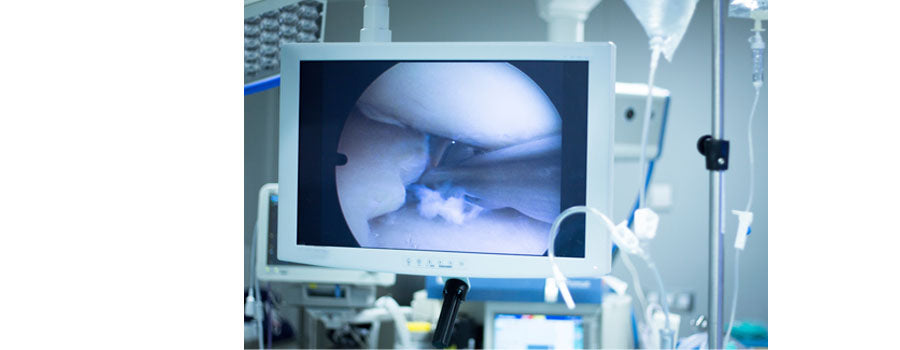

A meniscus tear is a common type of damage to cartilage in the knee.

Cartilage Injury

Cartilage damage in the knee can cause pain, swelling, and difficulty with movement.